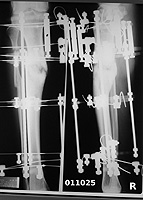

My 22-degree varus deformity of the tibia, the result of an earlier trauma injury, was corrected by Dr Tsuchiya and associates at Kanazawa University Hospital in Japan on February 7. Pre-op needle biopsy disclosed no infection around the fracture site. Bone scan tests with a radioisotope marker showed abundant blood flow around the fracture site. An Ilizarov frame mimicking the shape of the deformity was assembled based on the X-rays. All six screws of the former hardware, a titanium plate, were found to be loose. During surgery the tibia was found to be flexible enough to permit correction during the surgery. Bone graft material was harvested from the right iliac crest. A tissue culture of the plate from the previous, failed surgery revealed no infection. Antibiotic IV (Pansporin) was provided for five days, followed by oral Pansporin which continues. My temperature stabilized at normal within four or five days of the surgery, and there have been no signs of infection at the wire tracts. I started walking short distances three days after the surgery, and am currently undergoing physical therapy. The major limitations on my activity now are pain and stiffness, plus the usual post-op fatigue, but these are expected to diminish with time. The next step, of course, will be for regenerate to appear.

I wish to thank, again, the members of this group whose discussion of this case clarified the issues and helped me to select a treatment option. My selection of the Ilizarov technique was motivated primarily by the desire for a strong structural framework pending bone healing, and the documented boost in local blood supply stimulated by the Ilizarov device. The option I selected applies to the particulars of my own case, in which vascular damage and a previous failed surgery involving internal fixation figured prominently, and I do not attempt to draw any general conclusions from this one case.

Click Images to Zoom In

Pictures and X-rays are included. I will be glad to answer questions.